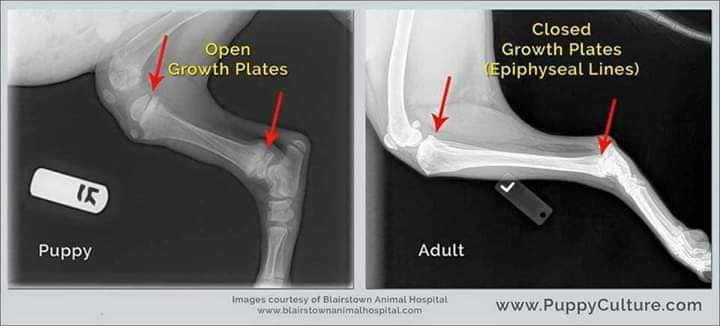

C'est quelque chose que tout le monde devrait voir.

Lorsque vous prenez vos chiots âgés de 8/12 semaines, veuillez garder cette image à l'esprit.

Leurs os ne se touchent même pas encore. Ils marchent si gentiment avec de grosses pattes souples et un mouvement bancal parce que leurs articulations sont entièrement constituées de muscles, de tendons, de ligaments recouverts de peau. Rien ne s'emboîte étroitement ou n'a encore de véritable prise.

Lorsque vous les laisser forcer de manière excessive ou si vous ne restreignez pas leur exercice pour les empêcher d'en faire trop pendant cette période, vous ne leur donnez pas la chance de grandir correctement. Chaque grand saut ou course de rebond excitée provoque des impacts entre les os. En quantités raisonnables, ce n'est pas problématique et c'est l'usure normale dans laquelle chaque animal s'engage.

Mais lorsque vous laissez le chiot sauter de haut en bas du salon ou du lit, ou que vous l' emmenez pour de longues promenades / randonnées, vous endommagez cette articulation en formation. Lorsque vous laissez le chiot se brouiller sur une tuile sans traction, vous endommagez l'articulation.

Un corps bien construit est quelque chose qui vient d'un excellent élevage et d'une excellente éducation - LES DEUX, pas seulement un.

Une fois adulte, vous aurez le reste de votre vie à passer à jouer et à vous engager dans des exercices à fort impact. Alors gardez le calme pendant qu'ils sont encore de petits chiots